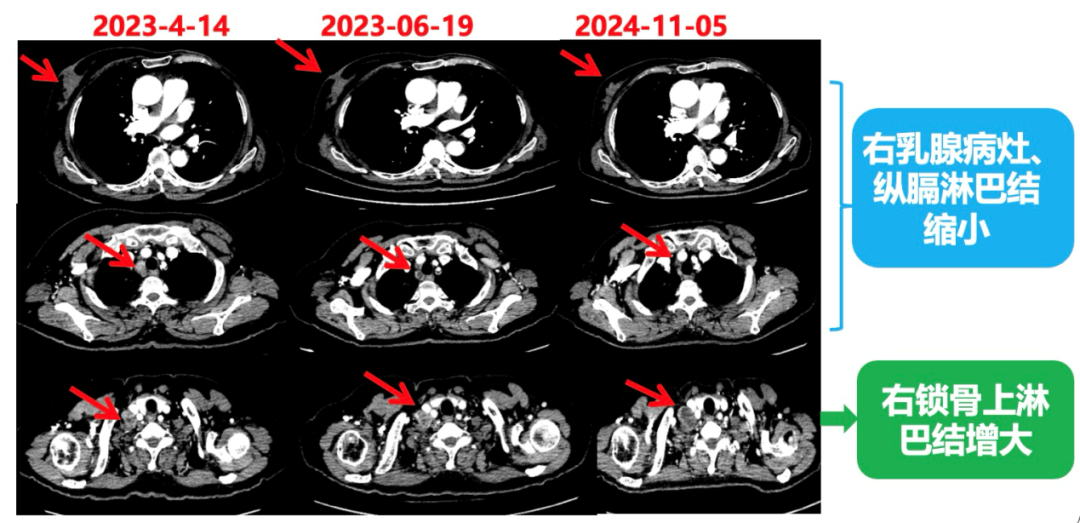

1.右乳外上象限乳腺癌病灶(22*16mm),对比2023-04-14 CT(26*24mm)较前缩小,FDG代谢活跃。右侧腋窝小淋巴结(5mm),较前稍缩小,代谢不活跃。右侧锁骨上区、上纵隔淋巴结转移瘤(24*18mm),现大小同前相仿,代谢活跃(SUV:6.7)。

患者已接受胃癌根治术,术后通过PET-CT对病灶情况进行了评估。目前患者采用哌柏西利联合氟维司群方案治疗,乳腺病灶已明显缩小,但锁骨上淋巴结、纵隔及肺门淋巴结未见缩小。为进一步为患者制定更精准的治疗方案,龚畅教授与曾银朵教授组织了第二次多学科联合会诊。

2024-11-5复查CT:右乳外上象限占位(11mm×9mm),较前明显缩小;上纵隔及右肺门多发淋巴结转移缩小;右锁骨上区淋巴结较前增大。余部位未见肿瘤转移及复发征象。

患者右锁骨上淋巴结较前增大,乳腺病灶明显缩小,针对是否需要进行锁骨上淋巴结及乳腺手术,龚畅教授和曾银朵教授又组织了第三次多学科会诊。

影像科:CT显示右侧锁骨上区病灶增大主要表现为液化坏死改变,考虑为治疗后改变而非肿瘤进展所致。